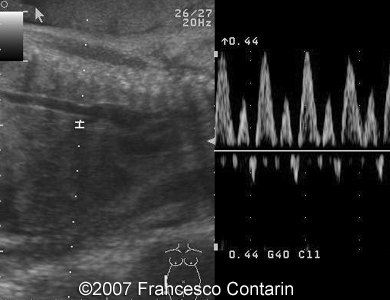

Images 7, 8. 29th week of pregnancy: abnormal ductus venosus waveform with A wave below the line (left); and fetal ascites (right).

7

8